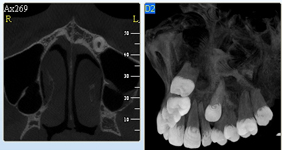

NewTom Giano

Jedná se o nejnovějším přístroj ze skupiny dentálních hybridních CBCT (3D) + 2D (pan i ceph) systémů. Opět umožňuje na základě jediného snímkování vytvořit všechny typy RTG zobrazení, které jsou pro lékaře potřebné. Používaná technologii tzv. „kuželového paprsku“ a speciální senzory pro minimální zátěž při snímkování pacienta.

Vyšetření pomocí tohoto přístroje (nebo

3D DVT - NewTom) a získaná data používáme

pro každou implantaci, dále ve stomatochirurgii (zlomeniny čelistí, zuby moudrosti, cysty, onemocnění čelistního kloubu), ortodoncii (retinované zuby, nadpočetné zuby), parodontologii atd.